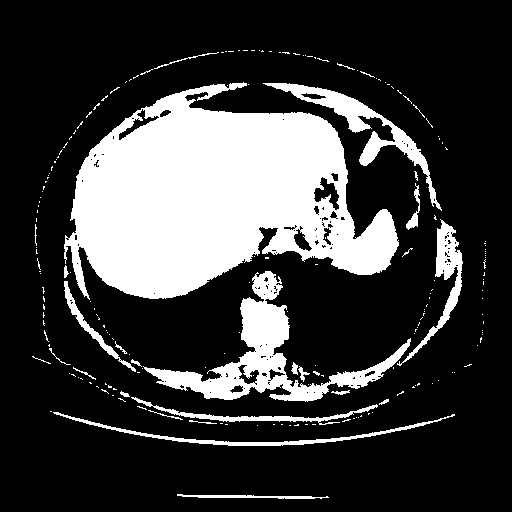

Original VENOUS CT scan

Full window (WL 1023.5, WW 4095 β†’ Low βˆ’1024, High +3071)

Actual HU range: [-1024.0, 3071.0]